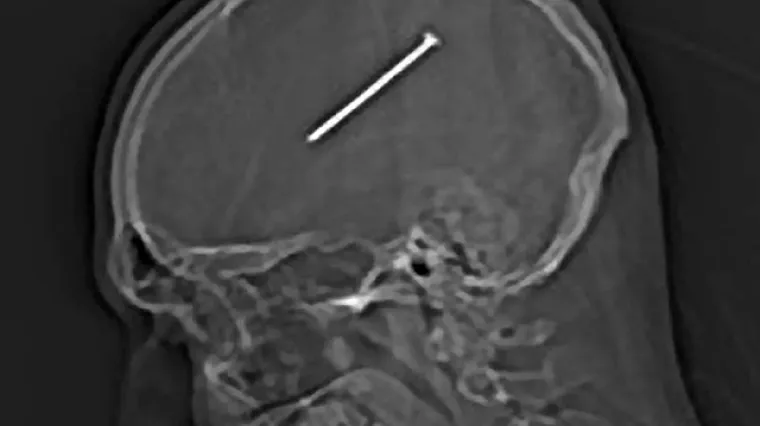

Zabio si čavao u glavu, a da to nije ni primijetio!

Jedan muškarac iz Chicaga nenamjerno si je ispalio sebi ispalio čavao, a ozljede nije bio ni svjestan.

Jedan muškarac iz Chicaga, sasvim je slučajno ispalio sebi čavao u lubanju, a trenutno se oporavlja u bolnici gdje mu je čavao odstranjen. 34-godišnji Dante Autullo radio je u svojoj garaži te se slučajno udario pištoljem za čavle. Taj udarac nije tada ni osjetio već je tek sljedećeg dana počeo osjećati mučninu. Kada je na nagovor zaručnice stigao bolnicu, rekli su mu da se čavao nalazi svega nekoliko centimetara od dijela mozga odgovornog za motoriku. Dante se sada osjeća dobro, može pomicati rukama i nogama te pričati normalno.